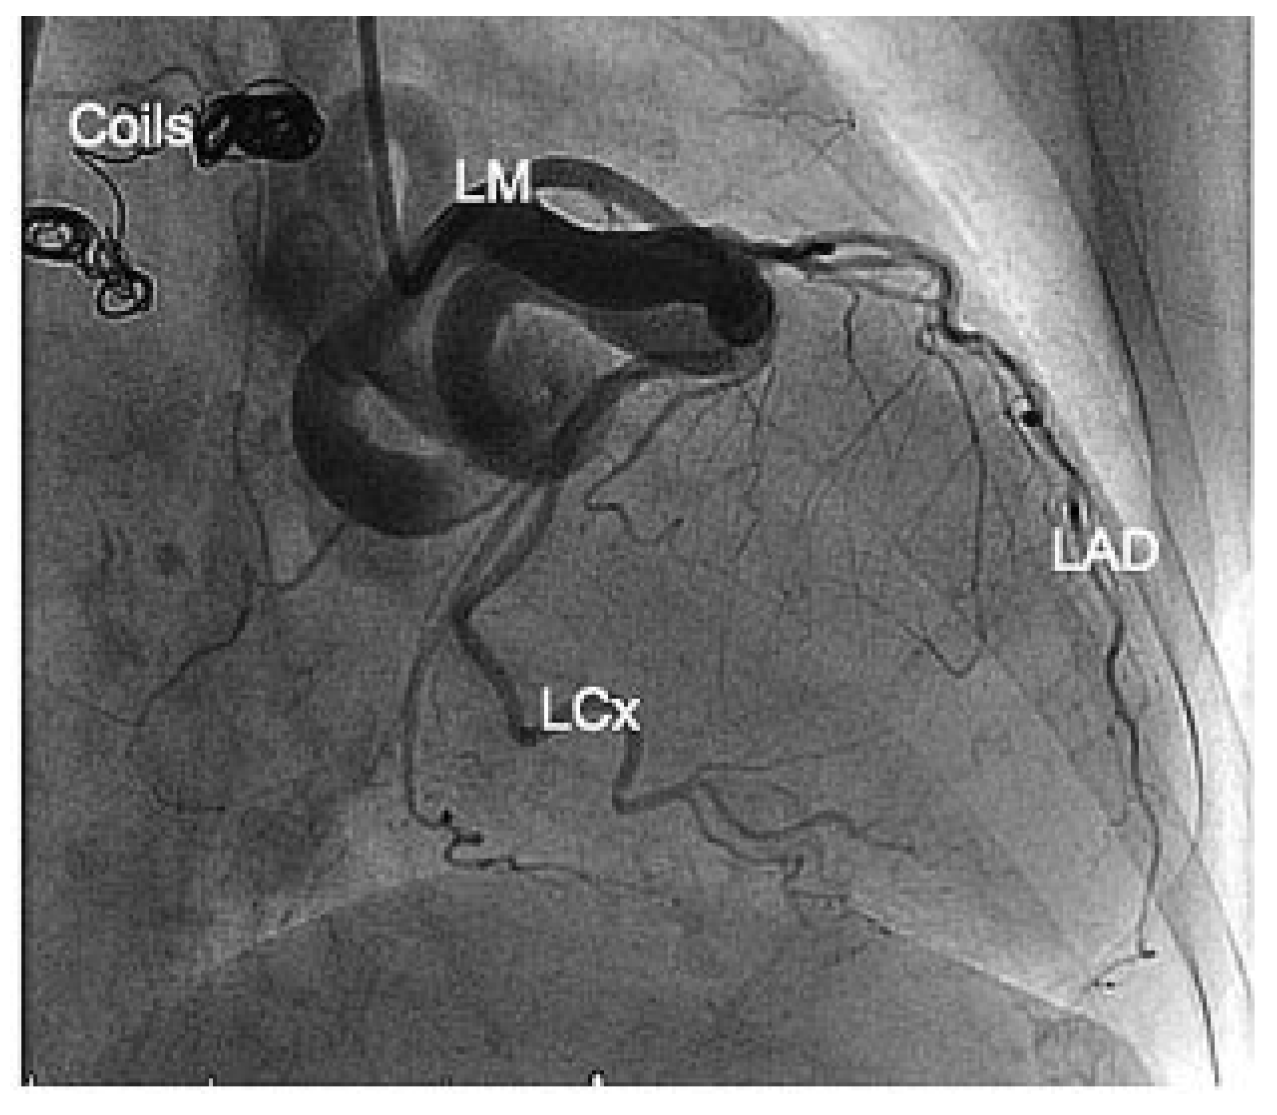

Figure 1.

RAO (A) and anteroposterior (B) caudal views. LM = left main coronary artery; LAD = left anterior descending artery; LCx = left circumflex artery; B = body of the giant fistula; C = collet of aneurysmal formation before reaching the right atrium.

The initial transthoracic echocardiography revealed both severe mitral and tricuspid regurgitation with bilateral atrial dilation and pulmonary artery hypertension estimated at 55 mm Hg. The left ventricular ejection fraction was normal. Under medical therapy (metoprolol, lisinopril and torasemide), the symptoms receded and the mitral regurgitation drastically diminished. A coronary angiogram was performed to rule out an ischaemic origin for the valvular disease. The latter revealed a giant coronary fistula arising from the mid circumflex coronary artery to the right atrium (Figure 1). A left-to-right shunt was estimated by Fick’s method (Qp/Qs 1.6) and the mitral regurgitation was graded as trivial.